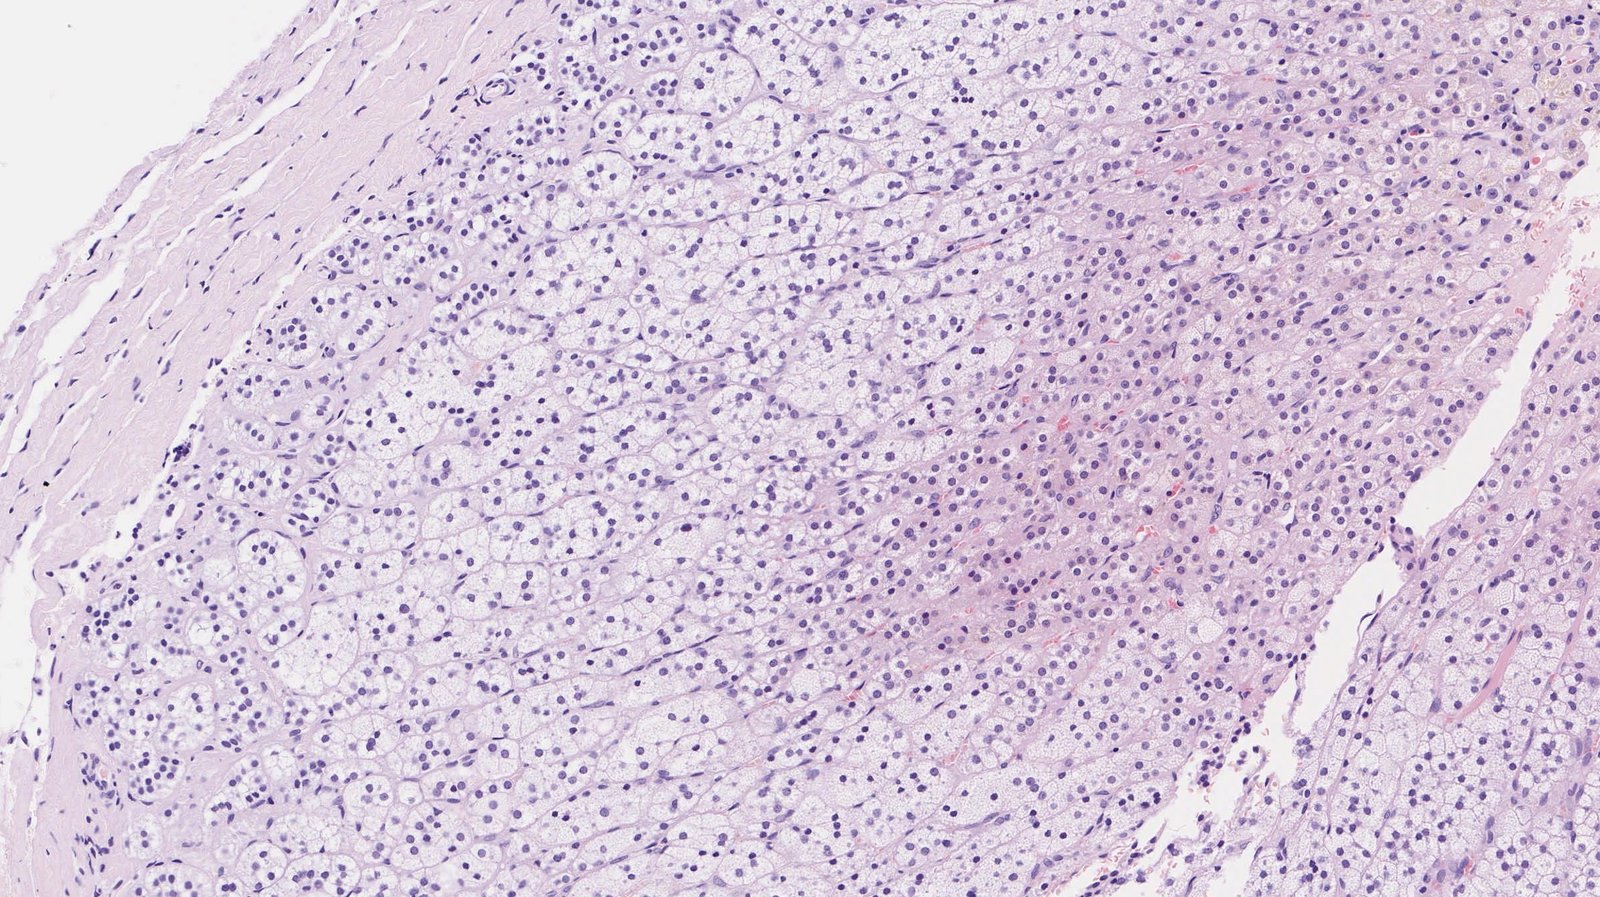

Adrenal cortex

- Overview: The adrenal cortex is surrounded by a fibrous capsule and composed of three main zones (or layers).

Zones

Zona glomerulosa

- Outermost layer

- Cells are arranged in oval clusters surrounded by connective tissue from the fibrous capsule.

- Main site of aldosterone production

Zona fasciculata

- Located between the zona glomerulosa and zona reticularis

- Cells are arranged in straight columns that are separated by small fibrous septa.

- Main site of glucocorticoid production

Zona reticularis

- Inner cortical layer

- Small cells are arranged in an irregular netlike formation surrounded by connective tissue and capillaries.

- Main site of androgen production

To remember the microscopic anatomy and functions of the adrenal cortex going from outside to inside, think βGFR, the deeper you go, the sweeter it gets: Salt (aldosterone, zona Glomerulosa), Sugar (glucocorticoids, zona Fasciculata), and Sex (androgens, zona Reticularis).β